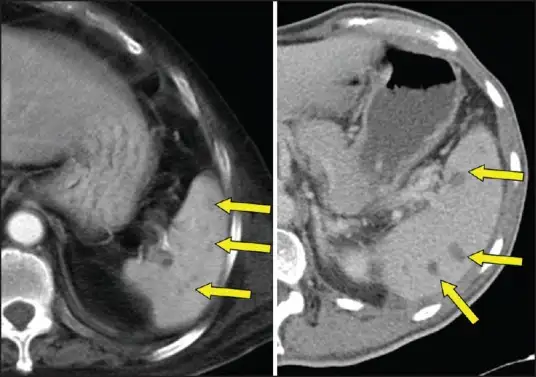

另一种可能性是,细菌在某些器官中形成了微小的脓肿——小到难以被检测,却又大到足以容纳一个休眠的细菌群落。这些脓肿可能位于前列腺、脾脏或肝脏深处,在数十年间不引起任何症状。然而,当条件合适时,脓肿破裂,细菌释放,一场致命的感染便开始了。

脾脏是另一个常见的目标。在类鼻疽患者中,脾脏脓肿的发生率远高于其他细菌感染。CT扫描常常显示多个小而离散的低密度病灶,这种表现被称为"靶征"。然而,如果没有考虑到类鼻疽的可能性,医生们可能会将这种表现误认为淋巴瘤或转移性肿瘤。